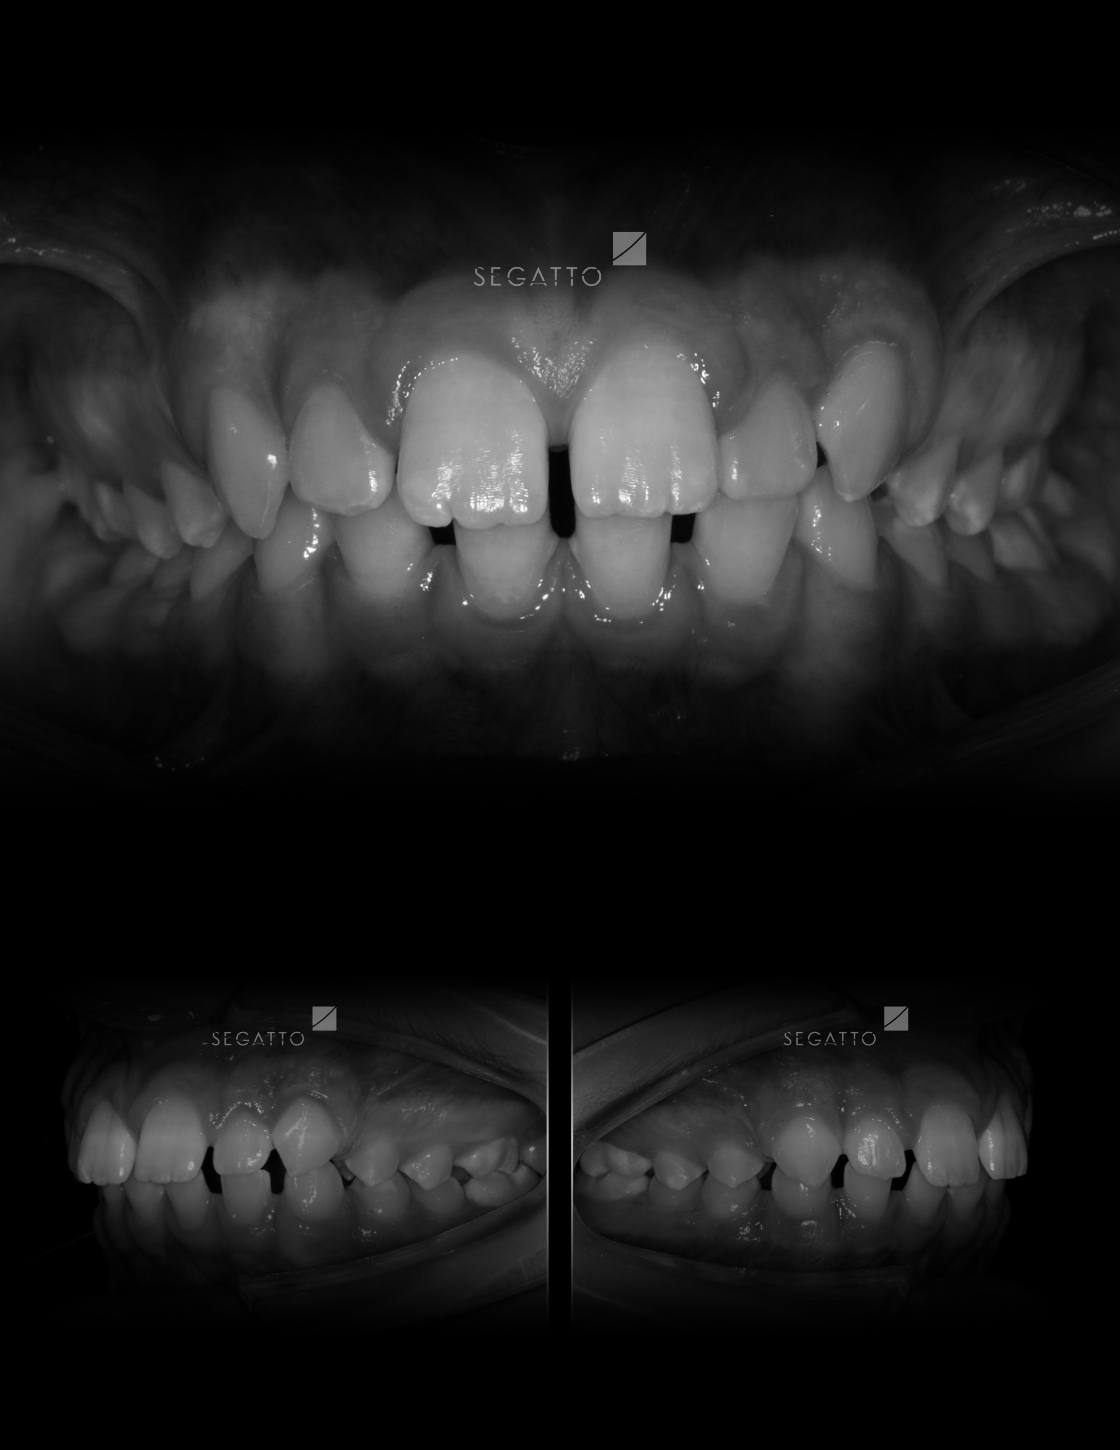

Orthodontics

Cases